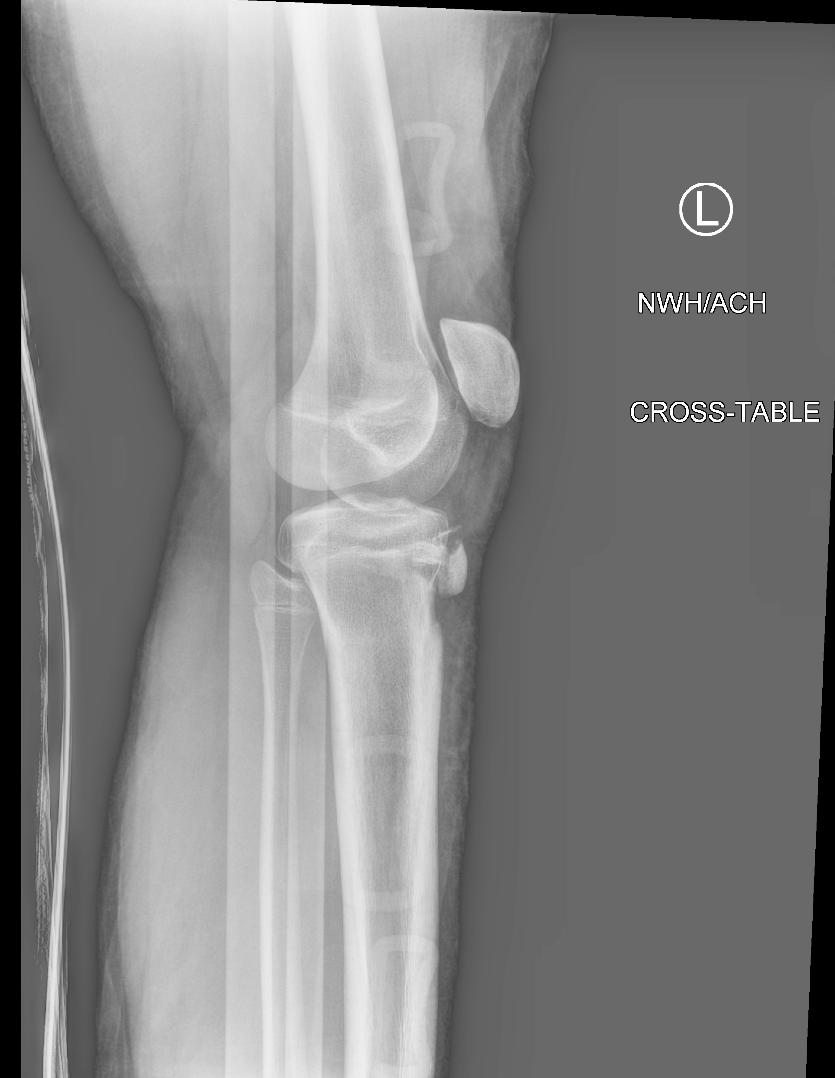

Findings

Bone

Growth plates, ossification centers, apophyses

Joints and alignment